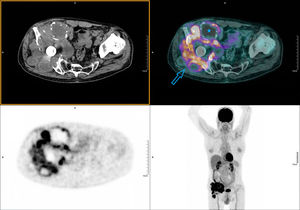

Presentamos el caso de un paciente de 66 años, recientemente diagnosticado de carcinoma vesical tras estudio de hematuria, que presenta cuadro de cojera y masa inguinal derecha indolora, de consistencia dura a la palpación. Como antecedentes personales destaca una artroplastia total de cadera derecha hace años por artrosis severa. La radiografía AP de cadera bilateral mostraba una importante destrucción ósea de la articulación coxofemoral derecha (fig. 1). Ante dichos hallazgos, se realizó PET/TC con 18F-FDG como estudio de extensión de proceso neoformativo primario vesical, con posibilidad de afectación metastásica ósea. En las imágenes a los 60min postinyección de la 18F-FDG se evidenció una gran masa de partes blandas multilobulada hipermetabólica en la región ilíaca derecha, que englobaba el material protésico y producía lisis de la pala ilíaca, con importante destrucción de la articulación coxofemoral (fig. 2). Se procedió a realizar biopsia ante los hallazgos indicativos de malignidad, con resultado de enfermedad de partículas por desgaste de los componentes de artroplastia. El paciente desestimó la posibilidad de revisión quirúrgica y se encuentra actualmente en seguimiento periódico.

PET/TC realizada a los 60min de la administración intravenosa de 200,14MBq de 18F-FDG. Imágenes de emisión y corregidas por atenuación con TC de baja dosis, desde la calota hasta el tercio superior de los muslos (protocolo whole body). Se aprecia una masa hipermetabólica en la región ilíaca derecha, multilobulada, de aproximadamente 15×13cm y alta intensidad de captación (SUVmáx 14,64). Engloba el material protésico de la cadera y se extiende cranealmente hacia el músculo ilíaco, produciendo destrucción ósea de la pala ilíaca, la articulación coxofemoral y el isquion (flecha). Asocia zonas ametabólicas indicativas de componente necrótico/quístico (estrella).